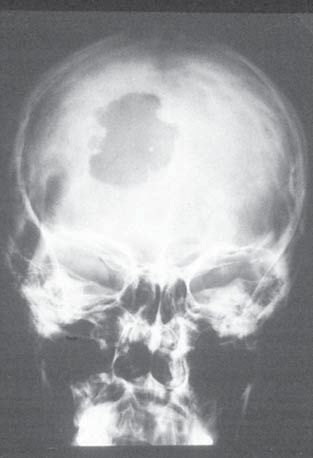

A three-year-old child presents with widespread lytic bone lesions. “Floating teeth” are seen on radiograph. Lytic lesions of the skull, exophthalmos and diabetes insipidis are noted.

Additionally, crusty red, weepy skin lesions at the hairline and extensor surfaces of the extremities, abdomen, and soles of the foot are discovered. Deafness also seen.

Hand-Schuller-Christian disease, multiorgan disease of childhood. A variant of langerhans cell histiocytosis.